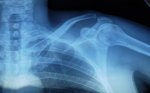

Jooooo, esto mete miedo, por lo que veo, hay gente que muy bien, otra que regular y otra que mal, cada cuerpo y cada lesión es diferente. Yo ayer caí haciendo Dh y la verdad, es que estoy preocupado por todo lo que he leído y me han dicho. La mía dicen que no hay que operar, pero tiene que confirmarla un traumatólogo, el que me miró era de medicina general. Mi preocupación es, si voy a volver a tener la misma movilidad en el brazo, y si voy a poder hacer descenso y otros deportes, el tema estético no me preocupa para la edad que tengo jajajjjajaja. Yo creo que parte de la culpa la tuvo el collarín para el cuello, y lo digo por el tema de que no me caí de cabeza contra el suelo, fue contra el manillar, pero me queda la duda. Os dejo una foto de una de las radiografías haber si es como las vuestras, ahora msimo estoy con un vendaje en forma de 8 que es un poco incómodo pero bueno uno se tiene que aguantar y estoy tomando ibuprofeno y nolotil para el dolor, solo lo tomo si me duele, aunque dolor no tengo mucho, eso sí, la primera noche fue un poco toledana jajajajj. Bueno, como soy un poco burramen, espero, que con rehabilitación y ejercicios, pronto pueda volver a mi actividad deportiva, haber el lunes que me dice el Trauma.